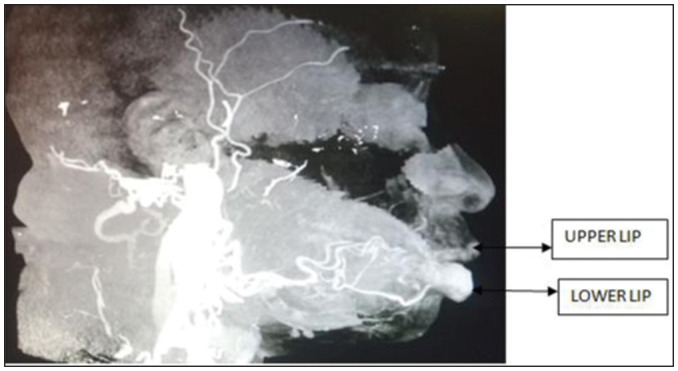

Calibre persistent artery of the lower lip is a vascular anomaly where the branches of the inferior labial artery maintain their size up to the submucosa of the lip. There is persistent pulsatile feeling, occasional ulceration, and recurrent bleeding. Doppler ultrasound and angiogram are used to confirm diagnosis. Before this case report, treatment of this condition has been surgical excision. We document the successful treatment with oral propranolol.